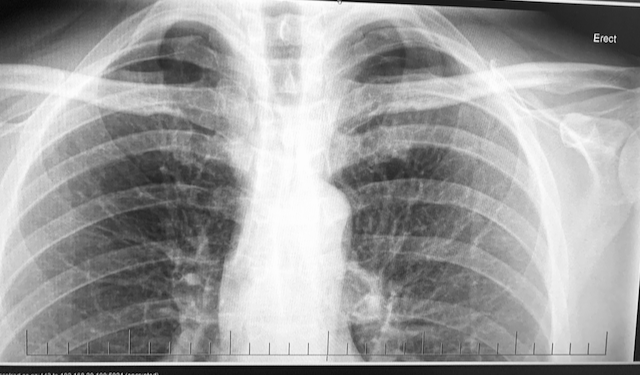

• Imaging (typically chest x-ray) remains key; consider CT if underlying lung disease suspected or to plan potential interventions. (The guideline covers this broadly in the pleural disease context.)

1. Confirm diagnosis (clinical + chest x-ray).